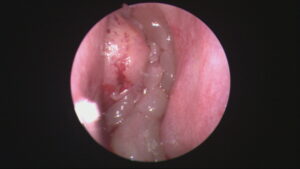

Endoskopik sinüs cerrahisi 1970’li yıllarda tanımlanmış ve kısa sürede yaygınlaşmıştır. Bu cerrahi yöntem fizyolojiye uygun olması sebebi ile çok etkili olmuş ve kronik sinüzitin tedavi yaklaşımını tamamen değiştirmiştir. Bu sebeple sinüzit tedavisinde kullanılan eski cerrahi yöntemlerin hemen hepsi kısa sürede terk edilmiştir. Bu cerrahi yaklaşımda temel mantık minik kamera uçları ile burun içini görüntüleyerek, sinüslerin tıkanmış olan doğal kapılarını açıp genişletmek, osteitli dokuyu çıkarırken, kemik yapıları kaplayan mukozayı mümkün olduğu kadar korumaya dayanmaktadır. Sinüs mukozaları korunduğu için zaman içinde mukus taşınması fonksiyonu yeniden başlar ve normal fiyolojik döngü elde edilebilir. Özellikle anatomik bozukluklara bağlı kronik sinüzit sorunu böylece tamamen ortadan kaldırılabilir ve bu hastalarda kronik sinüzit tekrarlamaz.

Endoskopik sinüs cerrahisinde ameliyat tamamen burun içinden yapılır. Cilde ve kemik dokulara kesi yapılmaz. Gereksiz doku çıkarılmaz ve bu nedenle ameliyat sonrası iyileşme daha kısa sürede ortaya çıkar. Burun içinin çok net bir görüntüsü büyütülerek monitora aktarıldığı için göz ve beyin ile ilgili komplikasyonlardan uzak durmak mümkün olur. Ameliyat burun ve sinüslerin fizyolojisine uygun olduğu için kronik sinüzitin tekrarlama ihtimali çok düşüktür.